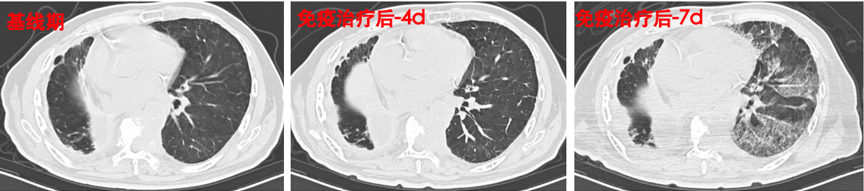

杭州市萧山区第一人民医院曹建华教授团队介绍了一例Ⅳ期肺癌患者在免疫治疗过程中发生免疫相关性重度肺炎的诊疗经过。来自复旦中山irAEs MDT团队的呼吸与危重医学科胡洁教授对该病例免疫治疗相关不良反应的鉴别、诊断、治疗、疗效评估等多方面进行剖析,并提出irAEs处理过程中需实施边治疗边诊断边修正的策略,且糖皮质激素的减量过程需要缓慢,同时需要警惕随着病情的发展是否有其他系统或器官的免疫相关不良反应发生。

患者肺部影像的变化过程